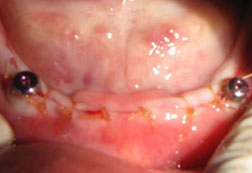

A dental implant is a titanium rod that is gently placed directly into the jawbone to act as an anchor to support one or more crowns or a denture. Each implant can usually be used to support up to two false teeth.

Implants can also be used as anchors to improve the stability and retention of loose dentures. Patients find great improvements during speech and eating, increased comfort and renewed confidence. We can often remove the tooth and fit a dental implant at the same appointment